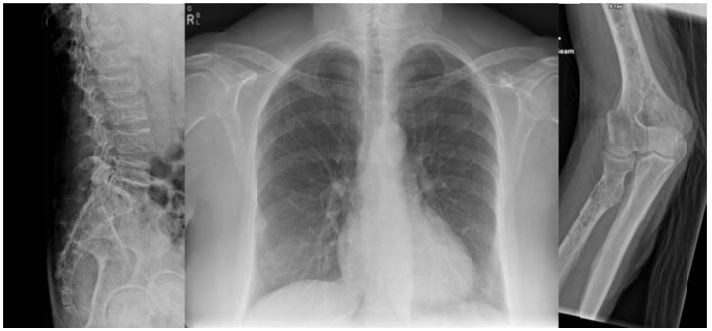

Radiograma: